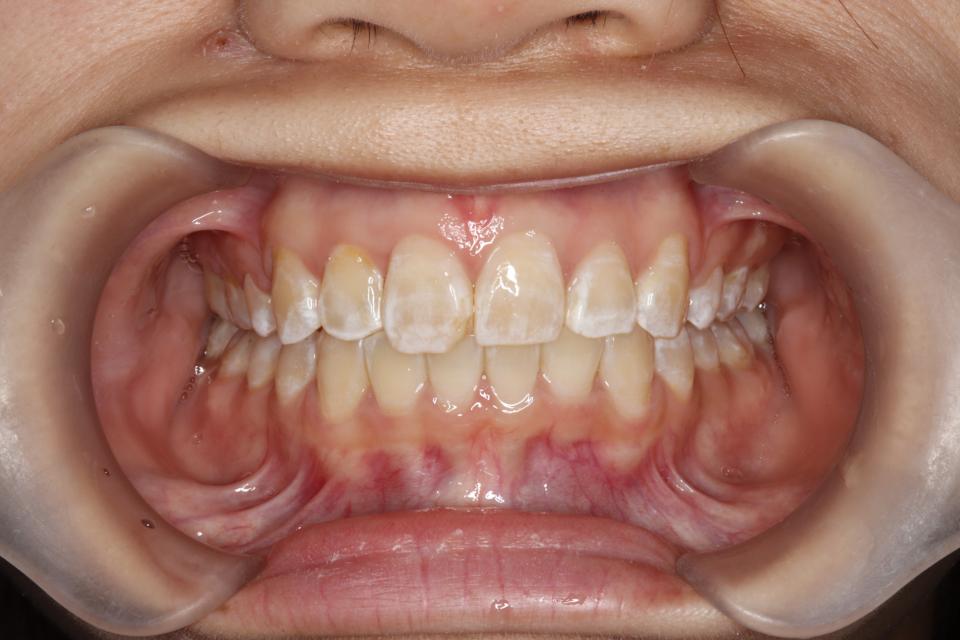

がたがた(叢生)のワイヤー矯正治療例(抜歯あり)

矯正治療後

上左右4番抜歯をして、上下の歯にワイヤー(マルチブラケット装置)をつけて治療しました。

きれいに並びきるために歯のやすりがけ(IPR)も行っています。

歯並びを並べる治療は終わり、現在は前歯の裏側にワイヤーをつけ、それと同時に

取り外しのできる装置をはめることで後戻りの防止をして、

| 矯正治療期間 | 2年5か月 |

| 抜歯の有無 | 上左右4番抜歯 |

| 治療費 | 977500(検査/診断/施術料含む) |

歯の移動に伴い痛みを感じる場合がある 治療後保定装置を使わないと後戻りを生じる |